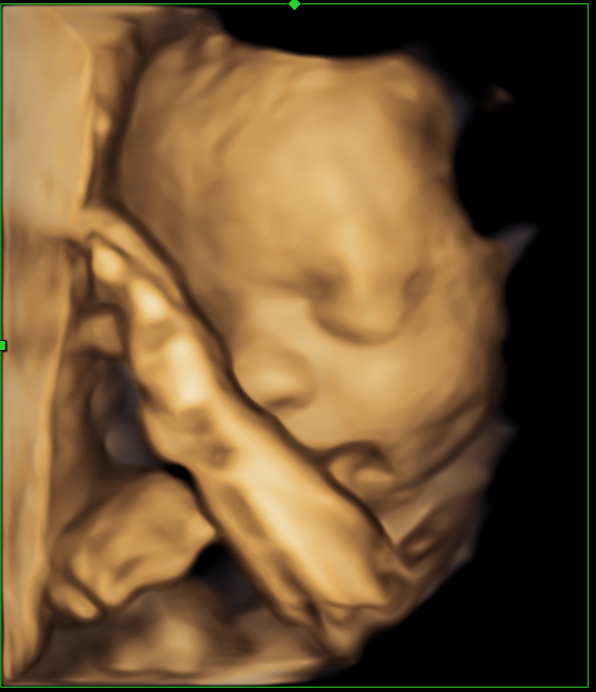

3D and 4D scans show the best results at 28 weeks or 24 weeks for twin pregnancy.

Our experienced Sonographers are able to provide 3D/4D ultrasound scans from 20 weeks and onwards, however we recommend that you choose the dates suggested above in order to obtain the best results.

- A 3D scan is a still image of a 3 dimensional picture of the baby.

- A 4D scan is a video of a 3 dimensional picture of the baby.

They are performed at the same time and recorded on to a USB.

A diagnostic well-being growth scan will also be performed and the anatomy will be checked such as stomach, kidneys, bladder and placenta position. Measurements will be taken and we will check the amount of fluid around the baby is normal.

3D/4D is dependent on the size and the position of the baby; other factors include the amount of fluid surrounding the baby and in some cases excess maternal abdominal fat. If we are complete unsuccessful then a complimentary scan will be arranged.